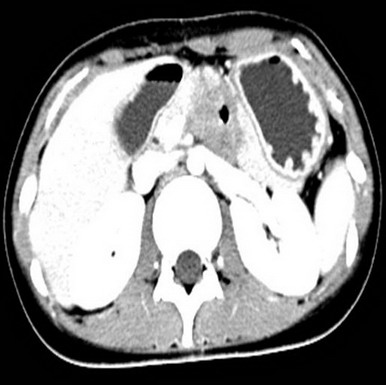

2009.6.23 腹部CT

腹膜后占位,性质待定,十二指肠局部穿透伴炎性包裹,十二指肠水平段梗阻,近端积液扩张,肝小囊肿(胰体后下方见不规则软组织密度影,大小约48mm*33mm,其内见气体密度影,增强扫描静脉期肿块明显不均匀强化,CT值约30HUPS 86HUCE,病变与十二指肠水平段、升段及胰腺分界不清,十二指肠水平段明显变窄,胃及近端十二指肠明显积液扩张。)